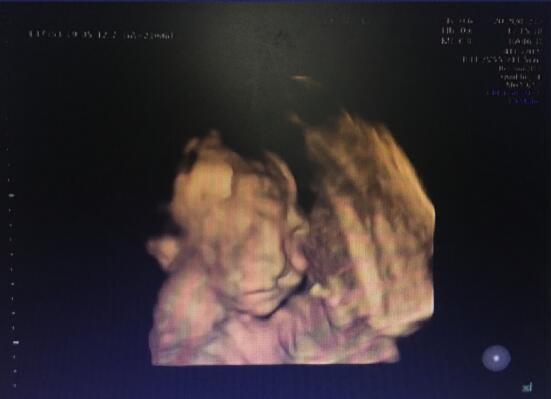

“胎兒嘴唇上有裂縫,為唇裂。”武漢仁愛(ài)醫(yī)院超聲影像科王娟主任說(shuō)道。

武漢仁愛(ài)醫(yī)院超聲影像科王娟主任正在為孕婦做檢查